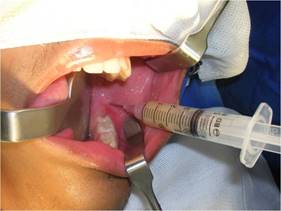

Bajo anestesia general, intubación nasotraqueal, tras antisepsia extra e intrabucal con solución de clorhexidina al 2 y al 0,12 %, respectivamente, se realizó la colocación del campo operatorio y el taponamiento del cruce orofaríngeo con "packing". Luego, se realizó una infiltración subperióstica a nivel de la región del trígono retromolar, donde había fluctuación por erosión cortical, con solución de clorhidrato de bupivacaína al 0,5 % con hemitartrato de epinefrina 1:200.000 para promover la hidrodisección perióstica y hemostasia. A continuación, se realizó la aspiración con una jeringa tipo luer de 10 cm³ con aguja 40X12 y se recolectó líquido seropurulento en cantidad abundante (Fig. 3).